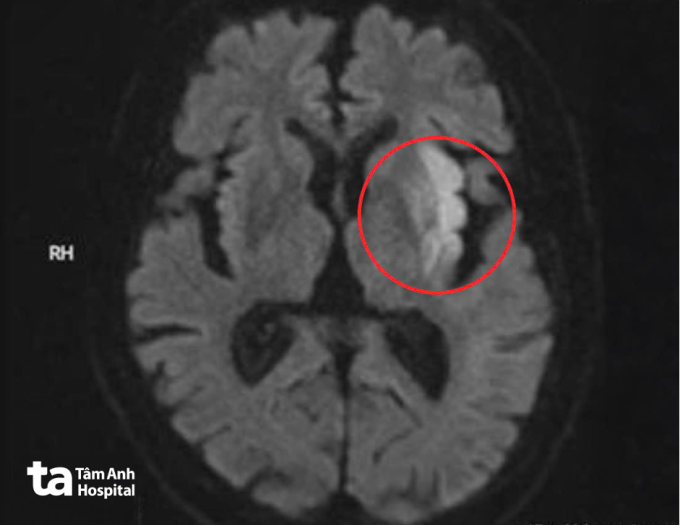

Bệnh viện kích hoạt quy trình “Code Stroke” tạo lối riêng cấp cứu đột quỵ. Kết quả chụp MRI 3 Tesla não của ông Trung cho thấy ổ nhồi máu cấp tại vùng nhân bèo, thùy trán và thùy đảo trái, kèm hình ảnh mất tín hiệu đoạn M1 động mạch não giữa trái, xác định tắc nghẽn mạch hoàn toàn.

Ảnh MRI cho thấy vùng nhồi máu cấp diện rộng ở bán cầu não trái, ảnh hưởng vùng vận động và ngôn ngữ của ông Trung. Ảnh: Bệnh viện Đa khoa Tâm Anh